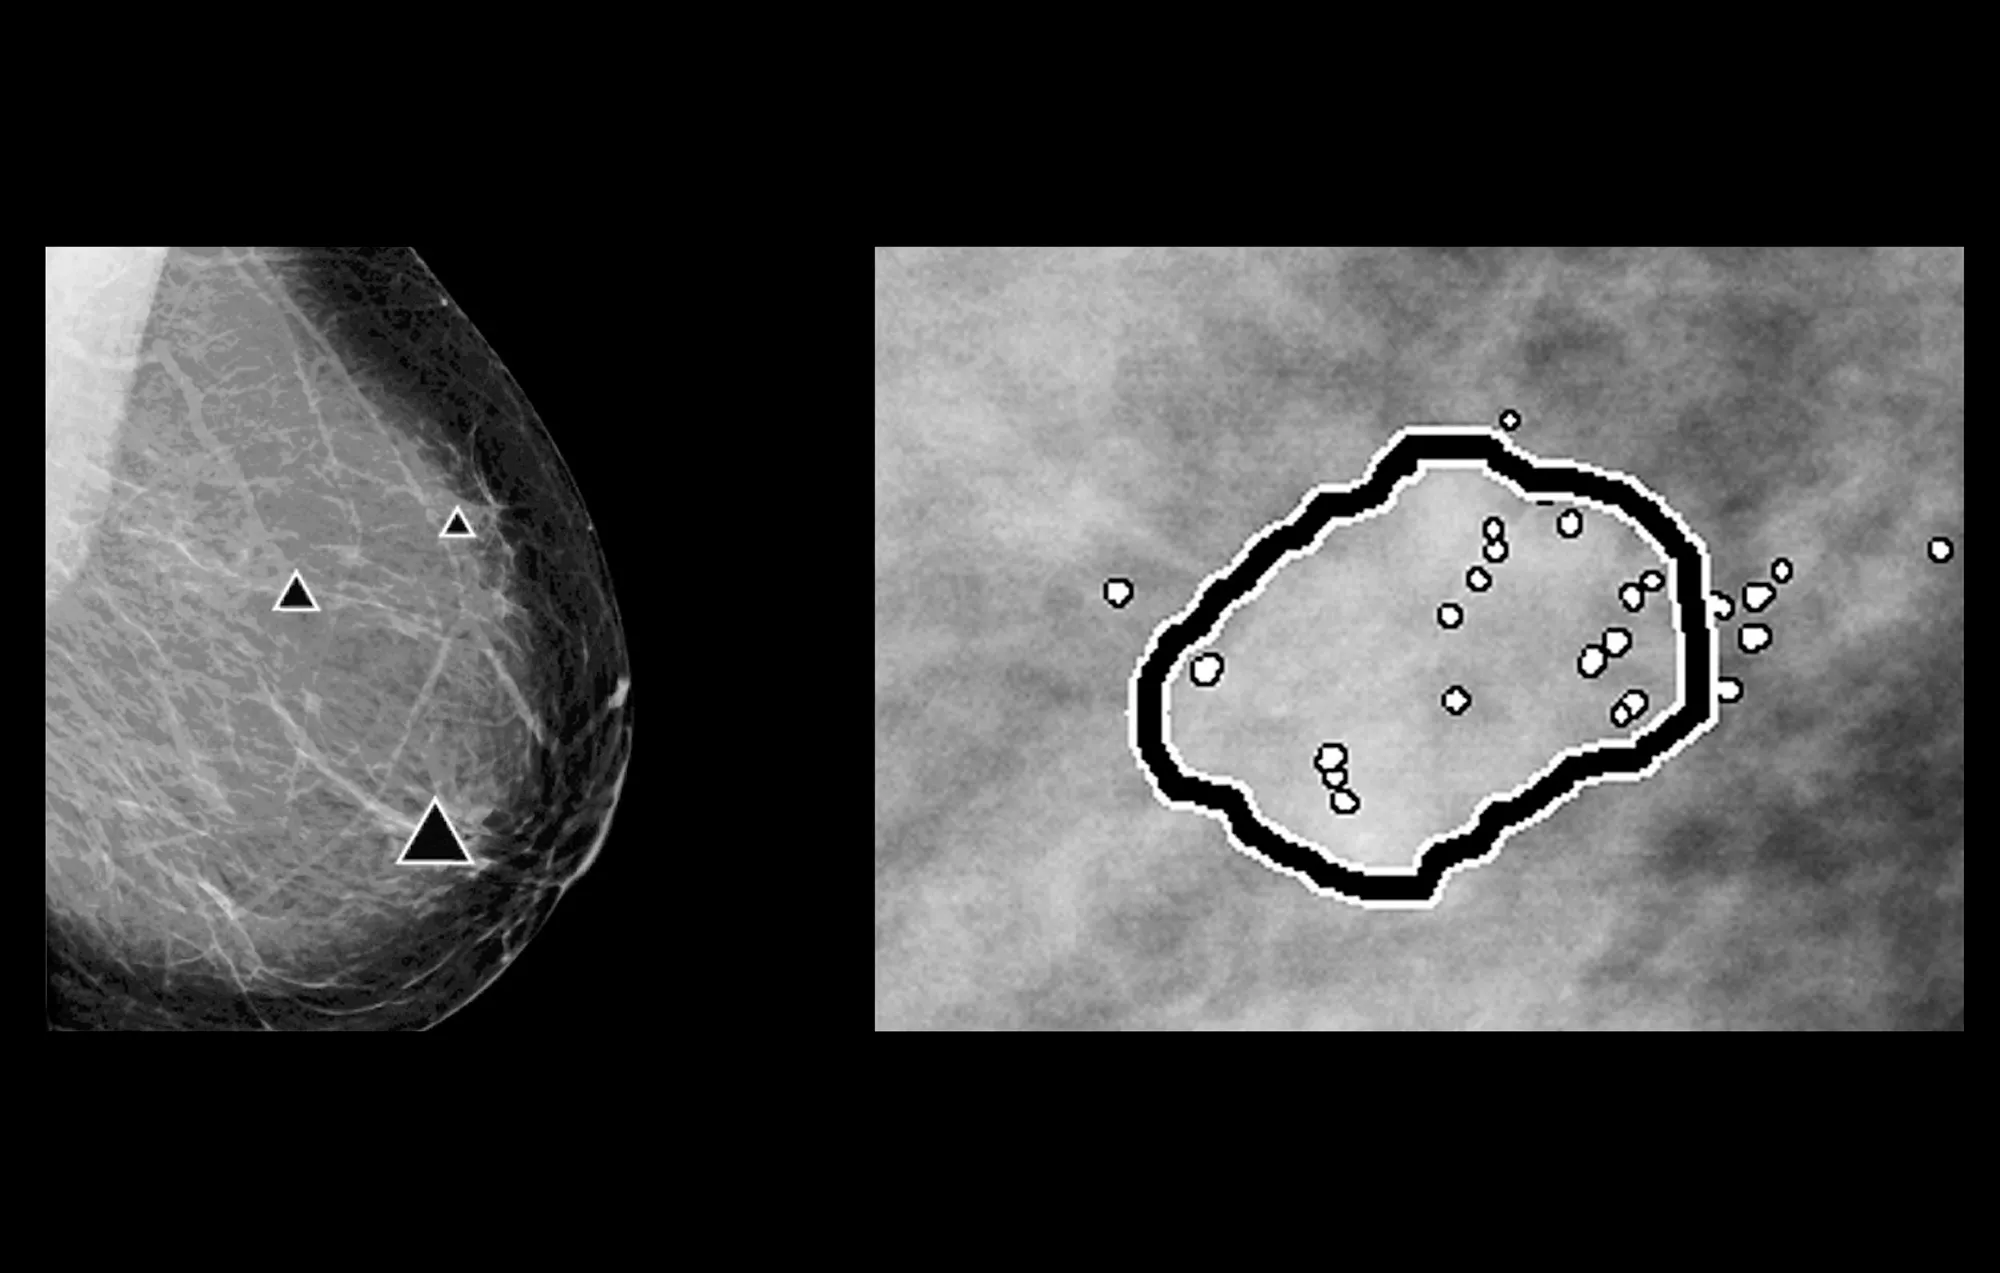

ImageChecker 2D CAD Technology searches digital mammograms for potential microcalcifications and masses, characteristics commonly associated with breast cancer.

• Regions-of-interest are highlighted for the radiologist’s attention

• Delivers highly sensitive results without excessive false-positive marks, streamlining case review2